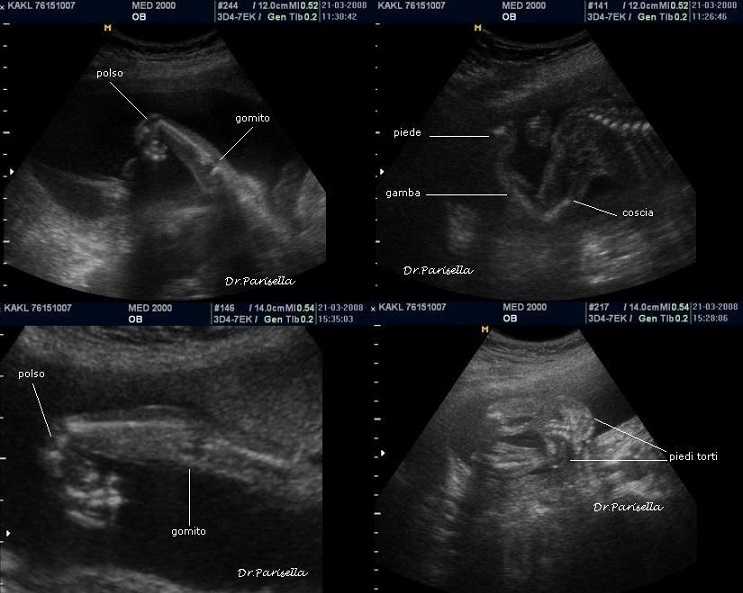

1) assenza di movimenti attivi fetali;

2) artrogriposi caratterizzata principalmente da contratture in flessione;